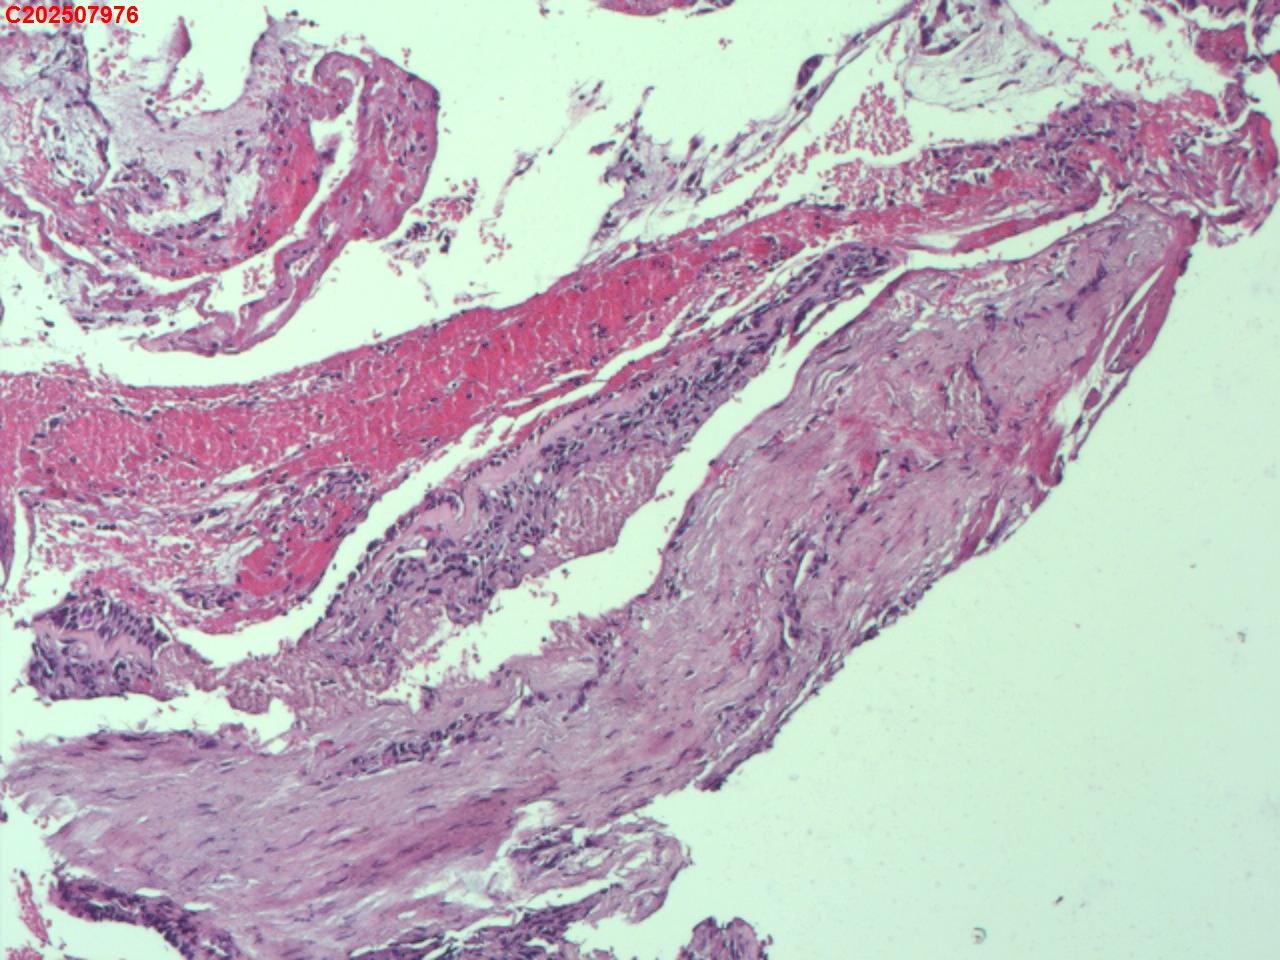

右肺上叶开口处 气管镜咬检

性别

男

年龄

65岁

临床诊断

一般病史

肺TB

标本名称

大体所见

右肺上叶开口上缘处可见肉芽增生,予咬检。

感觉:炎性纤维组织增生